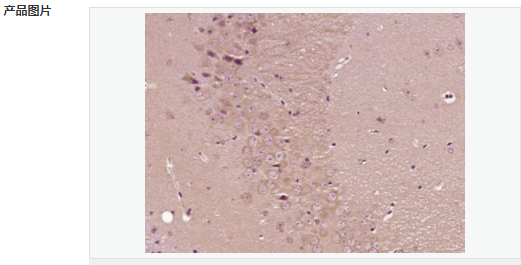

| 產(chǎn)品應用 | ELISA=1:5000-10000 IHC-P=1:100-500 IHC-F=1:100-500 IF=1:100-500 (石蠟切片需做抗原修復) not yet tested in other applications. optimal dilutions/concentrations should be determined by the end user. |

| 產(chǎn)品介紹 | This gene encodes a member of the fascin family of actin-binding proteins. Fascin proteins organize F-actin into parallel bundles, and are required for the formation of actin-based cellular protrusions. The encoded protein plays a critical role in cell migration, motility, adhesion and cellular interactions. Expression of this gene is known to be regulated by several microRNAs, and overexpression of this gene may play a role in the metastasis of multiple types of cancer by increasing cell motility. Expression of this gene is also a marker for Reed-Sternberg cells in Hodgkin's lymphoma. A pseudogene of this gene is located on the long arm of chromosome 15. [provided by RefSeq, Sep 2011] Function: Organizes filamentous actin into bundles with a minimum of 4.1:1 actin/fascin ratio. Plays a role in the organization of actin filament bundles and the formation of microspikes, membrane ruffles, and stress fibers. Important for the formation of a diverse set of cell protrusions, such as filopodia, and for cell motility and migration. Subunit: Associates with beta-catenin. Interacts with PLXNB3. Subcellular Location: Cytoplasm, cytoskeleton. Cell projection, filopodium. Cell projection, invadopodium. Cytoplasm, cytosol. Note=In glioma cells, partially colocalizes with F-actin stress fibers in the cytosol. Tissue Specificity: Ubiquitous. Post-translational modifications: Phosphorylation on Ser-39 inhibits the actin-binding ability of fascin. Similarity: Belongs to the fascin family. SWISS: Q16658 Gene ID: 6624 Database links: Entrez Gene: 6624 Human Entrez Gene: 14086 Mouse Omim: 602689 Human SwissProt: Q16658 Human SwissProt: Q61553 Mouse Unigene: 118400 Human Unigene: 289707 Mouse Unigene: 199526 Rat Important Note: This product as supplied is intended for research use only, not for use in human, therapeutic or diagnostic applications. FSCN1為細胞骨架肌動蛋白的一種,該蛋白有蛋白結合,橋連、肌動蛋白絲結合的功能。 主要參與細胞增殖、肌動蛋白細胞骨架組織和生物發(fā)生、肌動蛋白絲束形成。Fascin也是一種actin結合蛋白,它的功能是把F-actin聚集捆綁成束,與細胞的運動相關。病理情況下,各種惡性腫瘤細胞經(jīng)常高表達Fascin。 |